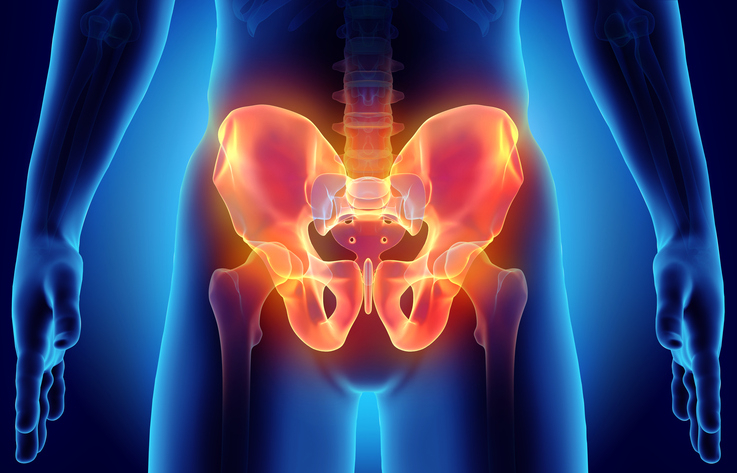

Jag har svårt att bygga baksida lår. När jag väl tränar baksidorna så har jag såpass bra kontakt att det börjar krampa. Efteråt kan jag knappt böja mig framåt. Ett återkommande problem är smärta i ländryggen, ibland så illa som ryggskott. Dock händer det inte mycket med muskelns utveckling. Tränar jag fel? ROBIN SVARAR: Baksida […]